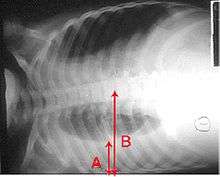

A chest radiograph is frequently used in diagnosis.[19] In people with mild disease, imaging is needed only in those with potential complications, those not having improved with treatment, or those in which the cause is uncertain.[19][48] If a person is sufficiently sick to require hospitalization, a chest radiograph is recommended.[48] Findings do not always match the severity of disease and do not reliably separate between bacterial infection and viral infection.[19]

X-ray presentations of pneumonia may be classified as lobar pneumonia, bronchopneumonia (also known as lobular pneumonia), and interstitial pneumonia.[51] Bacterial, community-acquired pneumonia classically show lung consolidation of one lung segmental lobe, which is known as lobar pneumonia.[29] However, findings may vary, and other patterns are common in other types of pneumonia.[29] Aspiration pneumonia may present with bilateral opacities primarily in the bases of the lungs and on the right side.[29] Radiographs of viral pneumonia may appear normal, appear hyper-inflated, have bilateral patchy areas, or present similar to bacterial pneumonia with lobar consolidation.[29] Radiologic findings may not be present in the early stages of the disease, especially in the presence of dehydration, or may be difficult to be interpreted in the obese or those with a history of lung disease.[20] A CT scan can give additional information in indeterminate cases.[29]